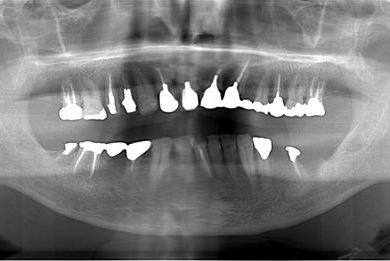

性別/年齢 男性 / 53歳

主訴 インプラント治療相談。

治療方針 骨再生法にて、インプラント治療を可能にする。

治療内容 インプラント2本(GBR)、ハイブリッドセラミッククラウン2本

総治療費 665,963円

治療期間 9ヶ月

治療前